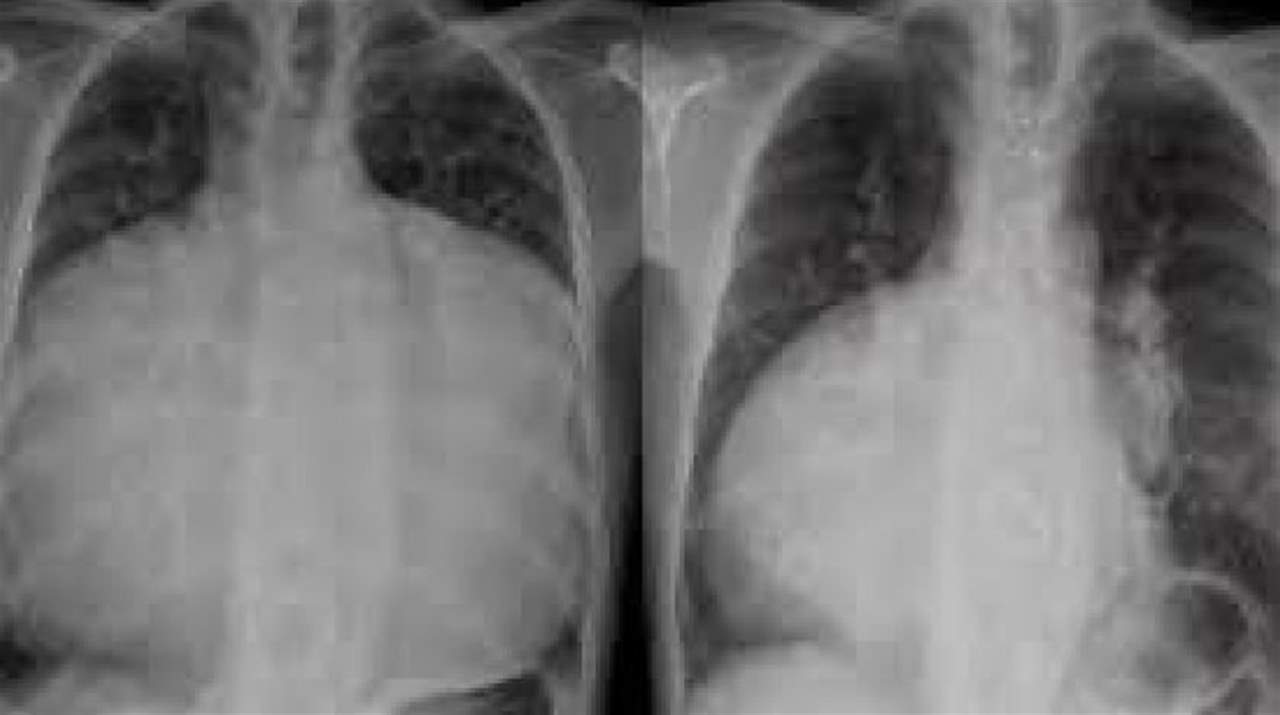

بعدما عانى الرجل من ضيق في التنفس استمر قرابة ستة أشهر شُخص رجل بحالة نادرة للغاية بعد أن وجد الأطباء أن قلبه قد تضخم لدرجة أنه ملأ تجويف صدره بالكامل، وفقاً لصحيفة «إندبندنت».

وكتب الخبراء عن حالة الرجل في منتصف العمر المجهول في المجلة الطبية البريطانية، وفق «الشرق الأوسط أونلاين» موضحين أن حالته تُعرف عموماً باسم القلب «من الجدار للجدار»، وغالباً ما يكون سببها شذوذ إبشتاين - وهو عيب في القلب يوجد عادة عند الرضع.

وأوضح الأطباء في المجلة، أنه تم اكتشاف الحالة بعدما عانى الرجل من ضيق في التنفس استمر قرابة ستة أشهر.

عندما أجرى الأطباء صورة أشعة سينية على الصدر، وجدوا ما هو بالأساس عبارة عن تضخم في القلب.

وتم قياس نسبة القلب والصدر (CTR) - التي تقيس نسبة القلب وإلى أي مدى يملأ تجويف الصدر. كشفت نسبة «1» عن أن التجويف الصدري للرجل ممتلئ بالكامل بسبب تضخم قلبه.